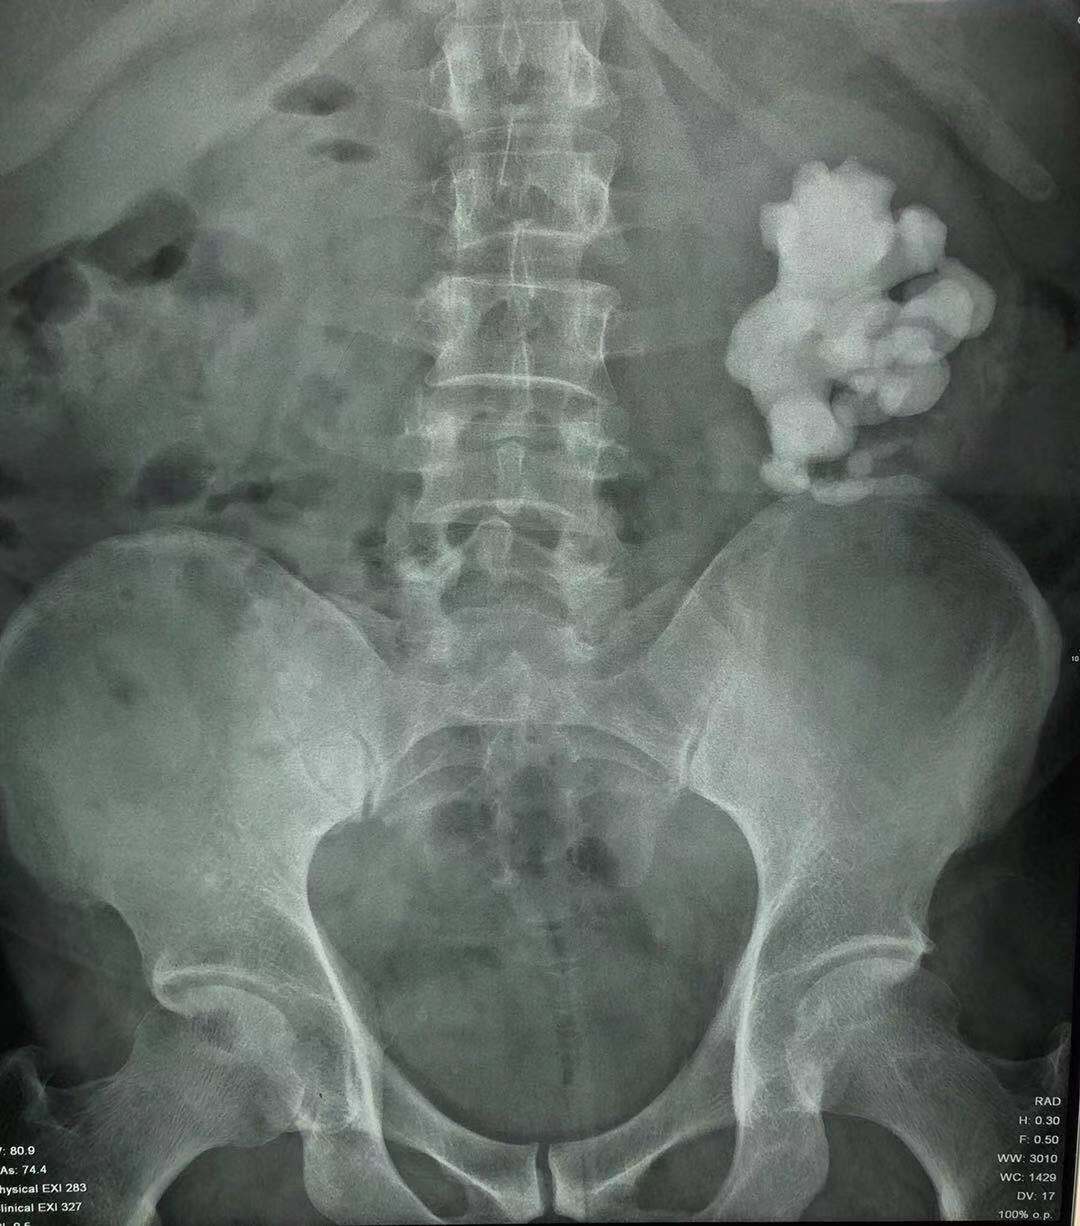

对于大多数尿路结石的病人而言,上述体外检测结石成分的方法并不适用,因为他们的结石从未离开过身体。不过,我们可以利用CT检查对体内的结石成分进行精确测量,同样能够知晓结石的真面目。